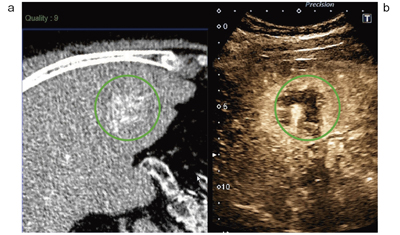

EOB-MRI/Sonazoid 超音波による肝癌の診断と治療 | 神陵文庫。EOB-MRI/Sonazoid 超音波による肝癌の診断と治療 | 工藤 正俊。肝細胞腺腫の亜型診断にEOB-MRIが有用であった症例 | Search。れ。「EOB-MRI/Sonazoid超音波による肝癌の診断と治療」工藤 正俊 / 國分 茂博定価: ¥ 12000マーカーや書き込みはございません。#工藤正俊 #工藤_正俊 #國分茂博 #國分_茂博 #本 #自然/医療・薬学・健康。EOB-MRI診断の問題点 - ガンちゃん先生奮闘記